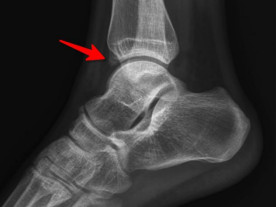

前方長骨刺

幾經(jīng)輾轉(zhuǎn),李先生來到廣安醫(yī)院就診,骨科中心主任羅軍副主任中醫(yī)師為他進(jìn)行了詳細(xì)專業(yè)的查體,結(jié)合影像檢查,診斷為右踝關(guān)節(jié)不穩(wěn)(距腓前及跟腓韌帶斷裂)、右踝關(guān)節(jié)創(chuàng)傷性關(guān)節(jié)炎。羅軍主任帶領(lǐng)大家詳細(xì)分析病情之后,決定為他施行踝關(guān)節(jié)鏡下病變組織清理和距腓前韌帶、跟腓韌帶重建術(shù)。

踝關(guān)節(jié)鏡見前方長骨刺

醫(yī)生們在手術(shù)中發(fā)現(xiàn),李先生的右踝關(guān)節(jié)軟骨損傷明顯,踝關(guān)節(jié)前方及內(nèi)外側(cè)均有不同程度的骨質(zhì)增生,相互撞擊引起疼痛,同時(shí)距腓前及跟腓韌帶斷裂。手術(shù)醫(yī)生利用磨鉆,小心翼翼將引起撞擊的骨刺一一去除,然后,修復(fù)了損傷的關(guān)節(jié)軟骨,最后,為他完成了距腓前和跟腓韌帶的修復(fù)。